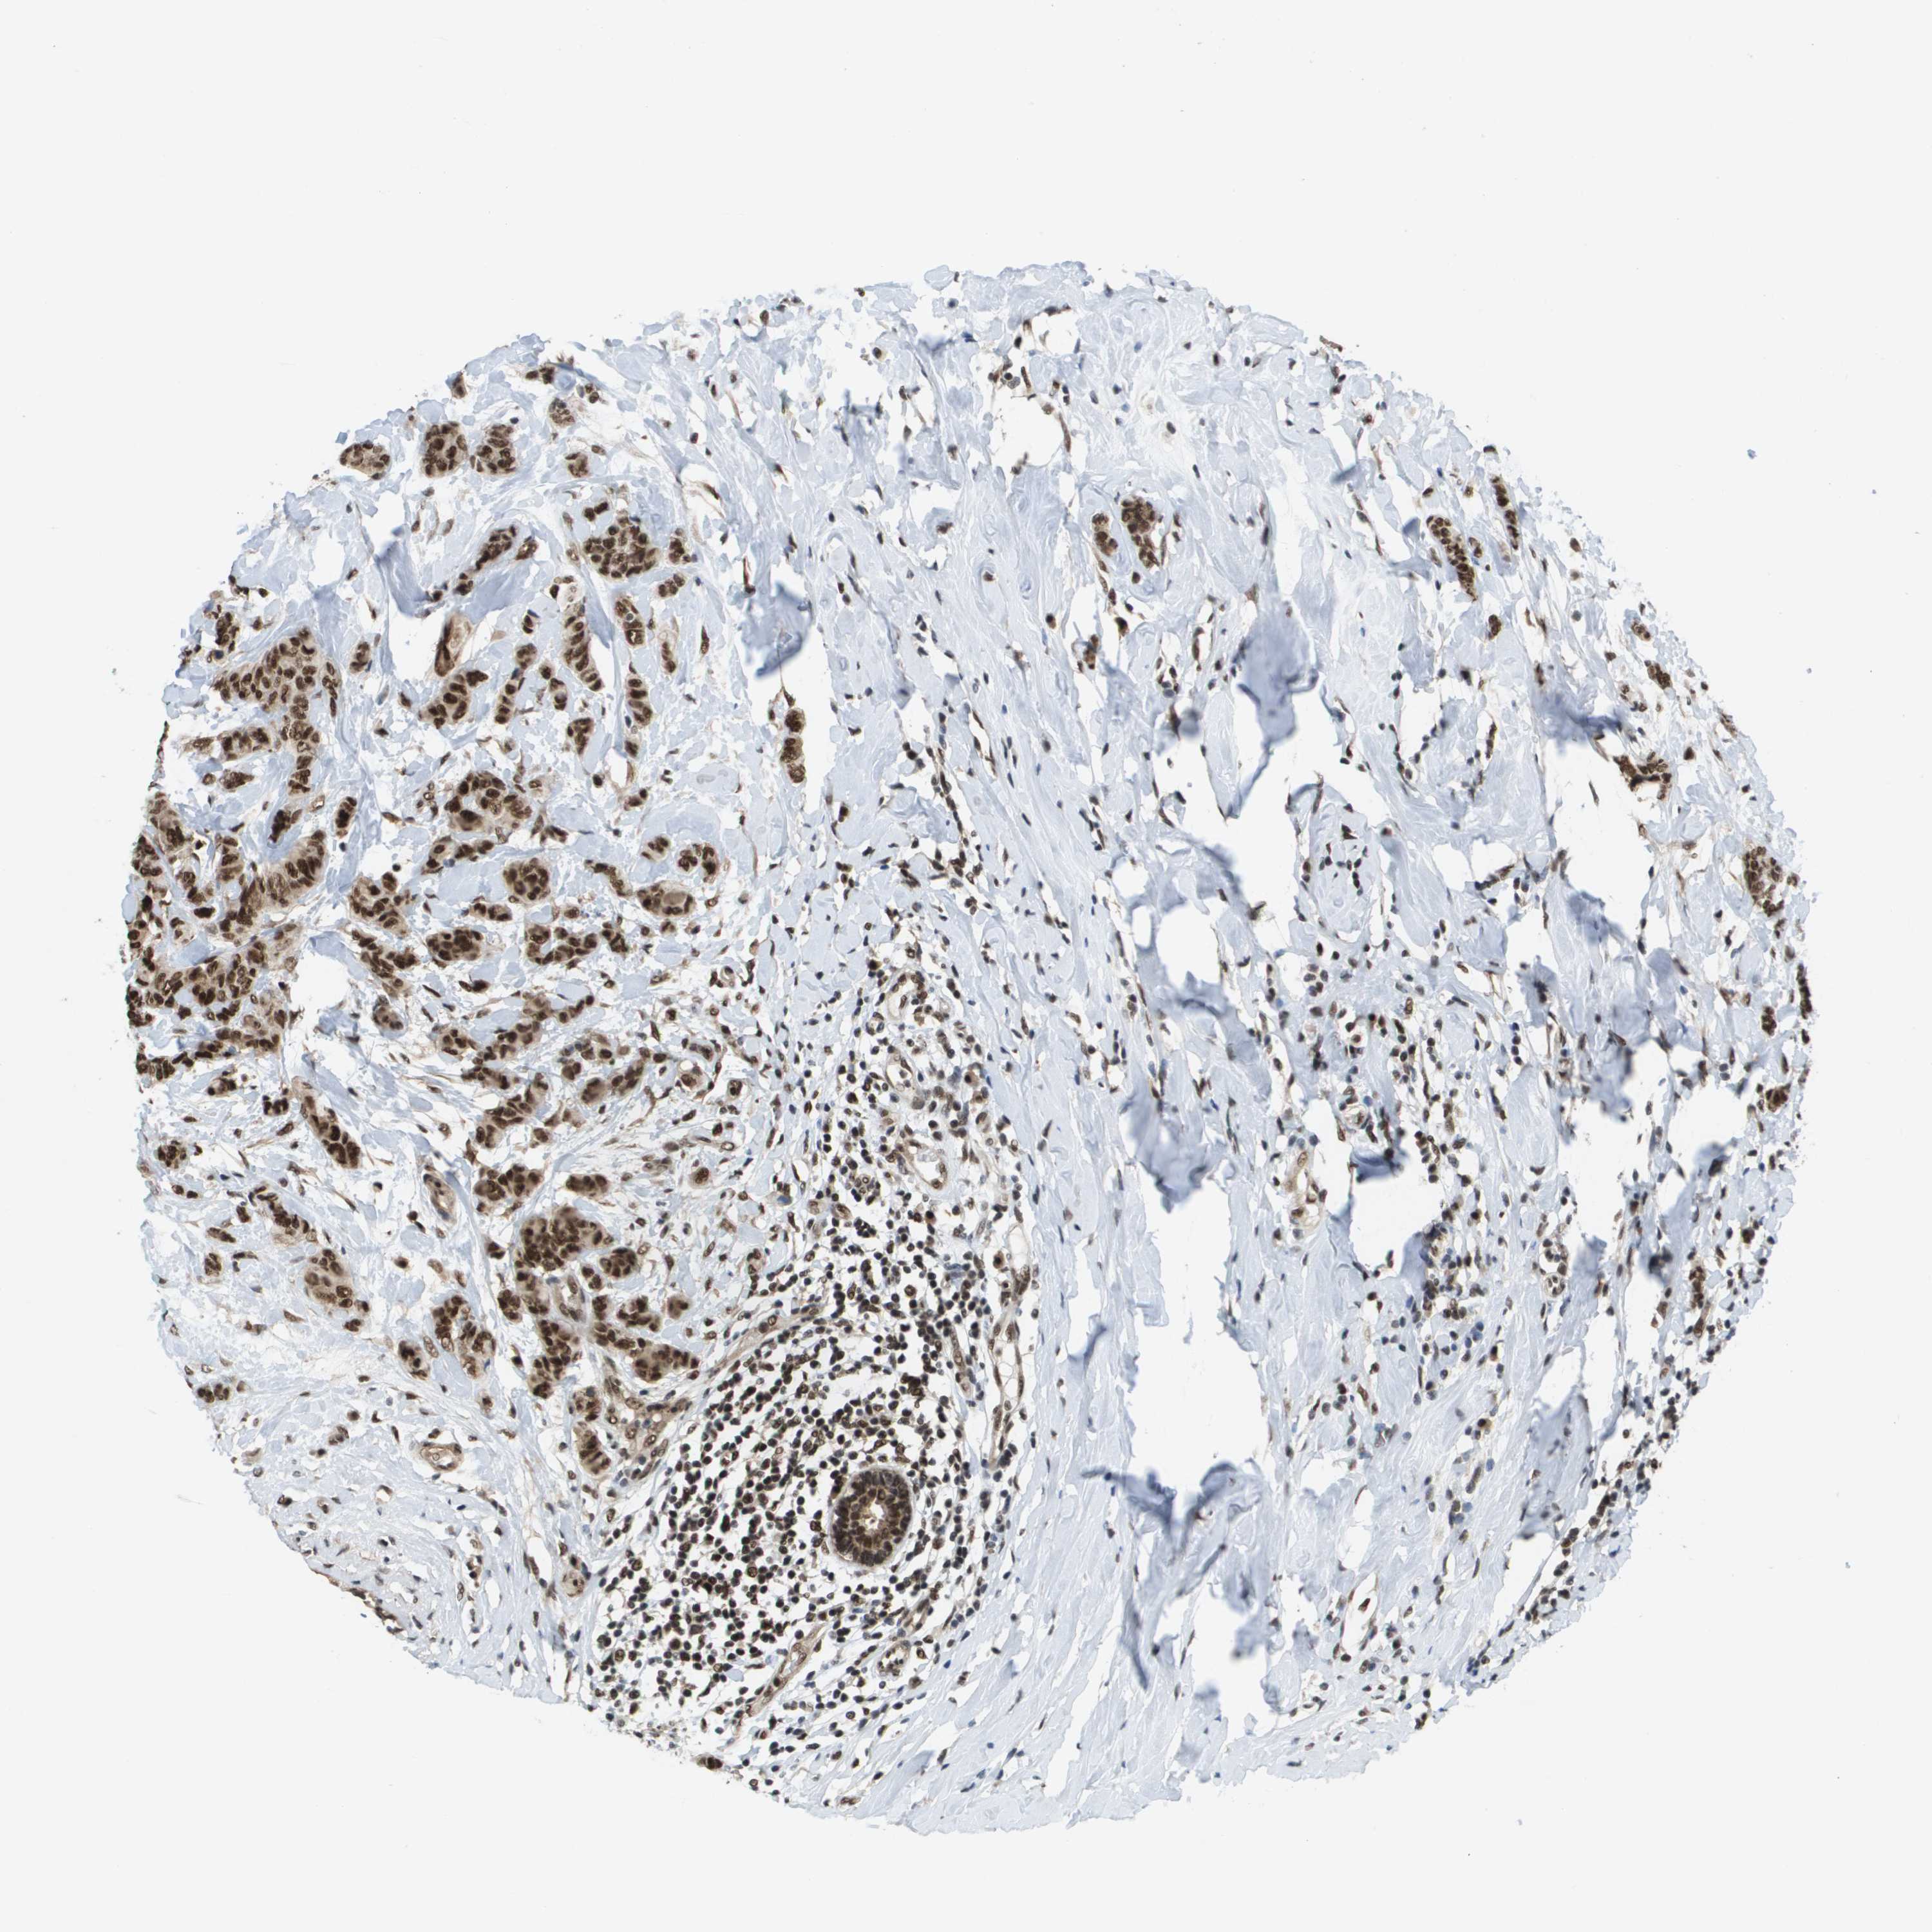

CANCER BREAST CANCER Show tissue menu

BRCA TCGA BRCA VALIDATION PROTEIN EXPRESSION